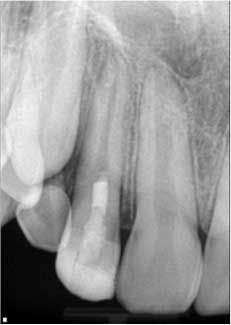

So how is the environment re-created? Let’s look at a case. Fig. 1 shows a lateral incisor that had sustained a concussive injury with an uncomplicated crown fracture. This 10-year-old boy presented to the office with complaint of pain, and swelling was present in the buccal vestibule. The tooth was diagnosed as having pulpal necrosis and an acute apical abscess. Due to the presence of an apical radiolucency and an immature apex, the regenerativeprotocol was chosen.Fig. 1: Tooth No. 7 showing incompletely formed apices and apical periodontitis. The patient also presented with pain to percussion and swelling.